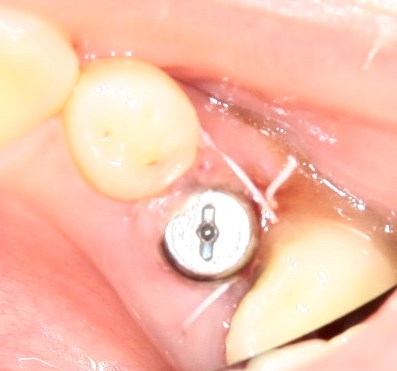

Немедленная имплантация — оптимальное решение в любой клинической ситуации